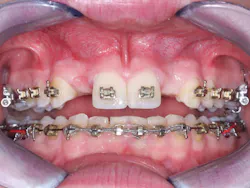

• Guided placement can offer significant advantages when placing multiple implants (figure 8).

Figure 8: Multiple implant placement is often difficult, and surgical guides can help place the implants in the best locations and parallel to one another.